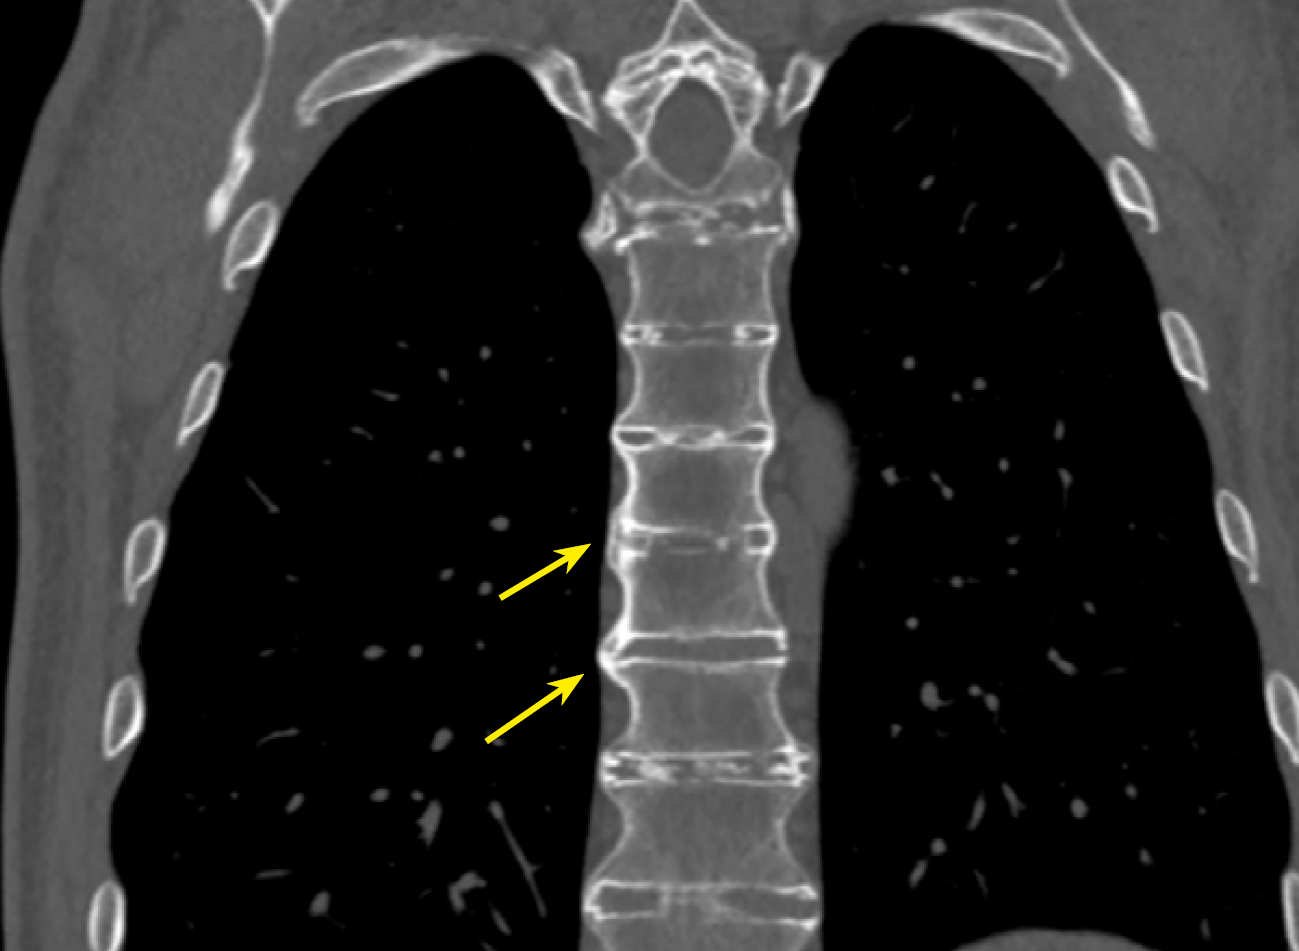

В нашем исследовании проведен анализ патологии позвоночника и суставов у пациентов с акромегалией. Спондилоартроз выявлен почти у всех пациентов — 95,9%, чуть реже визуализирован ОА реберно-позвоночных суставов 89,8% и ОА грудино-реберных суставов в 75,9% случаев (табл. 3, рис. 2–5).

Рисунок 4. МСКТ пациента А. с акромегалией 37 лет, коронарная проекция. Остеофиты по контурам тел позвонков, формирующие «костные мостики» (стрелки).

Figure 4. MSCT of patient A. with acromegaly, 37 years old, coronal view. Osteophytes along the contours of the vertebral bodies, forming "bony bridges" (arrows).